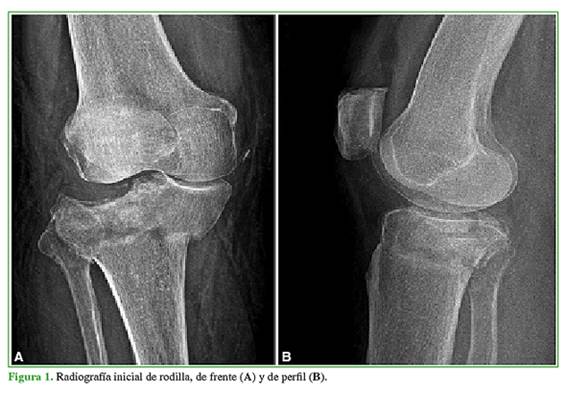

El par radiológico de rodilla y la tomografía computarizada revelan una fractura de platillo tibial clasificada como Schatzker VI (Figuras 1 y 2). Con la resonancia magnética de rodilla diferida, se diagnostica una lesión de tercer grado asociada del ligamento colateral medial.